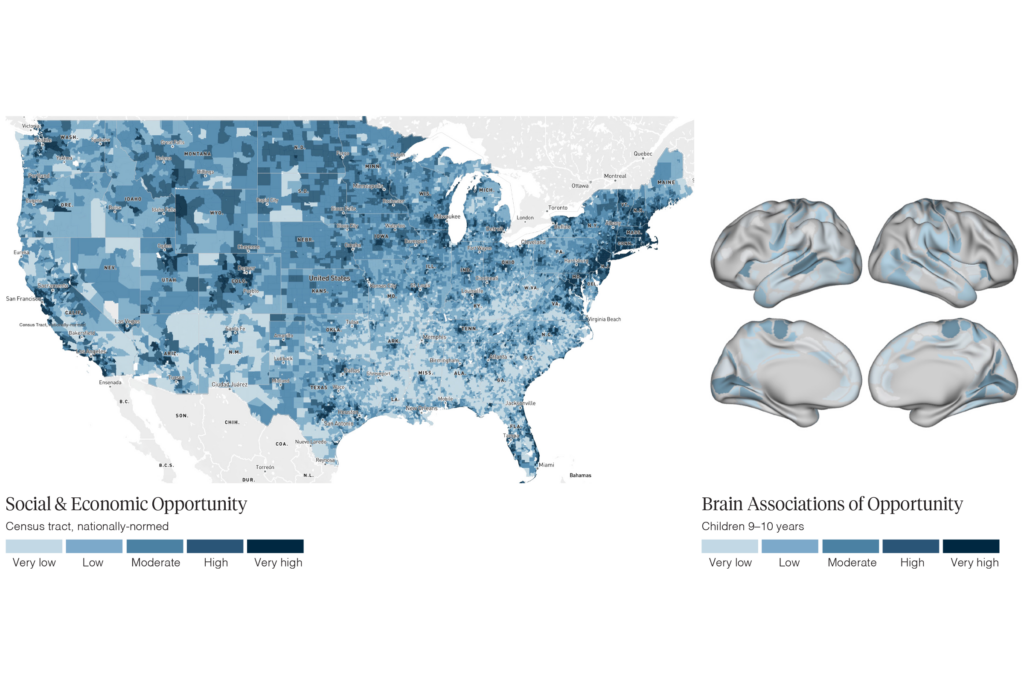

IQ’s link to brain structure, function in children may be a mirage

A child’s socioeconomic status, screen time and amount of sleep all show stronger associations with measures of brain structure and function, according to an imaging study of nearly 12,000 9- to 10-year-olds.

IQ’s link to brain structure, function in children may be a mirage

A child’s socioeconomic status, screen time and amount of sleep all show stronger associations with measures of brain structure and function, according to an imaging study of nearly 12,000 9- to 10-year-olds.